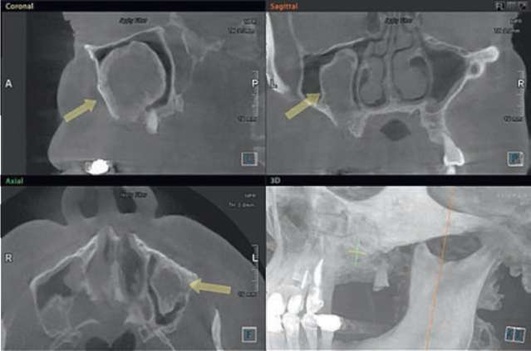

Дифференциальная диагностика

Следует проводить дифференциальную диагностику с массивными апикальными очагами, которые могут достигать действительно больших размеров, ремоделируя дно ВС, практические достигая орбитальной стенки ВС и вместе с этим не нарушая адекватную работу мукоцилиарного клиренса и дренажа ВС (рис. 5.88); а также с острым и хроническим остеомиелитом верхней челюсти, заболеваниями тройничного нерва, риногенным синуситом (рис. 5.89), опухолями (рис. 5.90), в том числе злокачественными новообразованиями, аллергическими воспалениями пазухи (см. рис. 5.89).

image

Рис. 5.88. Резидуальная киста верхней челюсти справа, ремоделирующая дно верхнечелюстного синуса

Для проведения дифференциальной диагностики с радикулярной кистой (одонтогенным апикальным очагом) и мукоцеле (ретенционной кисты), исходящей из мембраны Шнайдера, достаточно провести КЛКТ-исследование и акцентировать свое внимание на наличии или отсутствии кортикального венчика над верхним отделом кисты, в случае если он будет обнаружен, то при наличии одонтогенной причины (нелеченого или некачественно леченного зуба) можно утверждать, что данное образование имеет одонтогенную природу. Перфоративный синусит следует дифференцировать от радикулярной кисты, ремоделирующей дно ВС. Отличительный признак кисты - отсутствие попадания жидкости из полости рта в нос и воздуха из него в рот (см. рис. 5.88).

Рис. 5.89. Ретенционная киста правого верхнечелюстного синуса